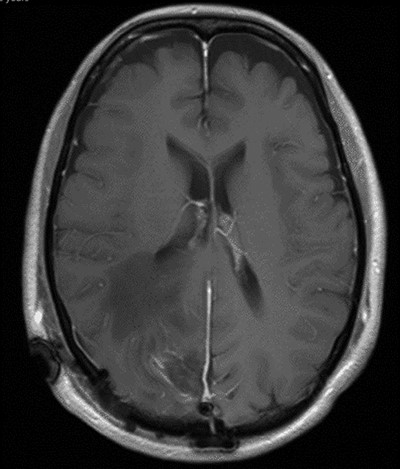

The operation was successful with a post-operative MRI within 48 h demonstrating complete resection of the tumour and resolution of the cystic lesions, but persisting intraparenchymal oedema (Fig. 3). The patient had an uncomplicated two-day stay in a neurosurgery high dependency unit postoperatively before being stepped down to the general neurosurgery ward. She was reviewed by the microbiology team and worked up for the source of infection. Blood cultures, urine cultures, CXR and transthoracic echocardiography were all negative for a source of infection. Intra-operative pus cultures isolated MSSA. The histopathology of the tumour was Meningioma WHO Grade 1 with large areas of necrosis and secondary abscess formation. She was discharged feeling well 5 days later after a satisfactory biochemical and clinical response. She was given a weaning course of steroids and a 6-week course of intravenous ceftriaxone via a PICC line as an outpatient as per microbiology advice. Ophthalmology assessment 3 months after discharge confirmed a left inferior quadrantonopia and preserved visual acuity. Repeat MRI and clinic review 8 weeks later showed no radiological residual tumour or oedema (Fig. 4), and the patient’s limb function recovered completely but had ongoing visual symptoms.

T1 weighted axial MRI post-gadolinium enhancement 8 weeks postdischarge. Right occipital postsurgical appearances are again demonstrated with reduction in the extent of vasogenic oedema. The enhancing rim that was present previously has retracted, with only focal curvilinear enhancement now evident in the right occipital lobe. These appearances are likely postsurgical/treatment related, and there is no convincing residual or recurrent disease.